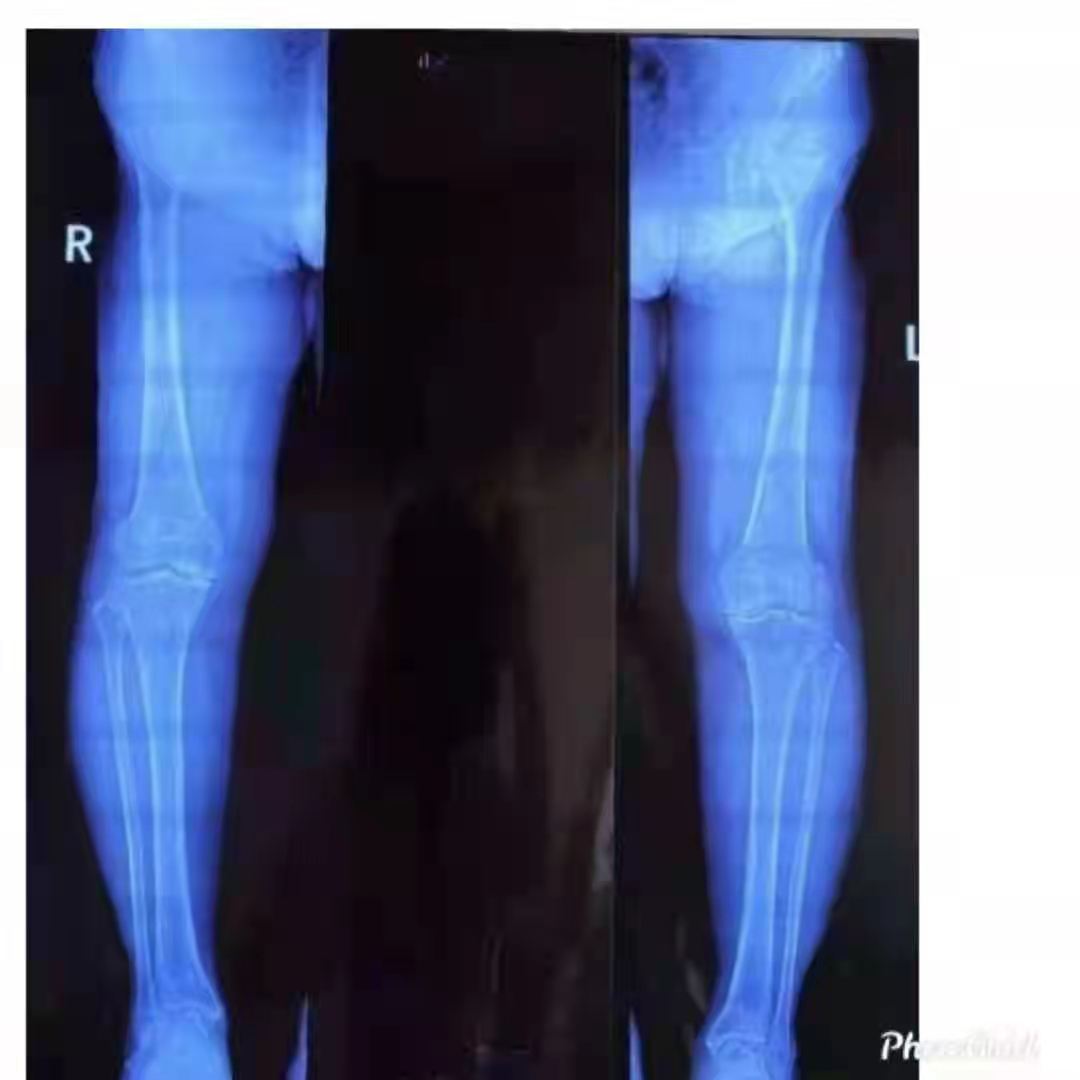

幸運的是,王女士慕名來到了山亭誠德骨科醫(yī)院,專家檢查診斷,發(fā)現(xiàn)王女士雙側(cè)膝關(guān)節(jié)內(nèi)側(cè)磨損嚴(yán)重,外側(cè)部分和前后交叉韌帶上好,因此采取雙側(cè)同期部分置換。應(yīng)用牛津單髁活動平臺,手術(shù)屬于保膝范疇,保留了好的部分,修補(bǔ)了磨損重的部分,病人感受好,恢復(fù)快,功能好。如果錯過這個修補(bǔ)的時機(jī),整個關(guān)節(jié)都磨損了,只能進(jìn)行全膝置換了。